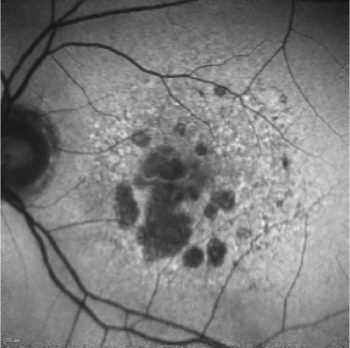

A multicenter study in Japan examined patients to understand geographic atrophy characteristics and progression rate.

You may be wondering: What is all this hype about geographic atrophy (GA)? If you are, let us look at the enigma.